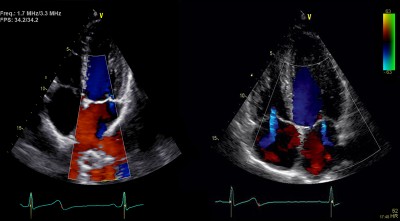

Ультразвуковое исследование сердца, или узи сердца, является одним из самых важных методов диагностики сердечно-сосудистой системы. Оно позволяет получить подробную информацию о структуре и функции сердца, выявить наличие аномалий, определить состояние клапанов и стенок сердца, а также оценить работу сердечных сосудов.

Процедура узи сердца является безопасной и болезненной. Она выполняется на специальном столе, в позиции лежа на спине. Врач, используя гель для лучшего контакта, наносит ультразвуковую головку на грудную клетку пациента. Затем, с помощью специального аппарата, врач получает изображение сердца на экране монитора.